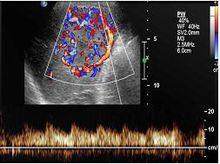

彩色都卜勒超聲(color Doppler flow imaging, CDFI)顯病灶中央有粗大的動脈向四周呈放射狀,動脈血流速高而阻力低為FNH的特徵性表現。